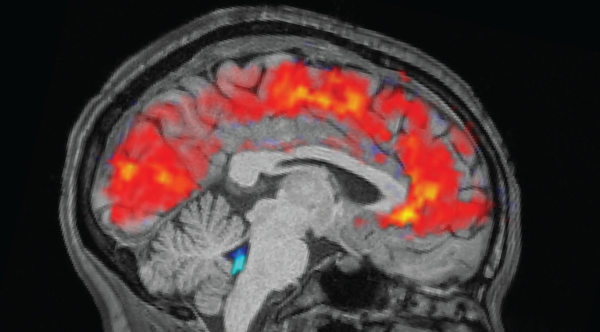

Study uncovers why the brain ‘blanks out’ when you’re depleted

Brain readings expose ‘dial’ that aids in preventing us from becoming disoriented

Study reveals why the brain ‘zones out’ when you’re exhausted

Brain scans reveal ‘dial’ that helps keep us from getting lost